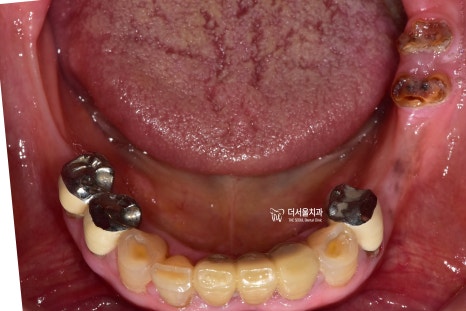

더서울치과에 오셨던 이 분의 경우,

구강 내 온전한 치아가 거의

없는 상태로 오셨었습니다.

이미, 치아의 결손 범위가 넓으셨으며

남아있는 치아들도 치근만

남아있는 곳이 거의 대다수입니다.

과거 부분 틀니를 오래 써오셨으며,

유지력을 얻게 도와줬던 surveyed crown 이

있던 위치는 치근만 남아있네요.